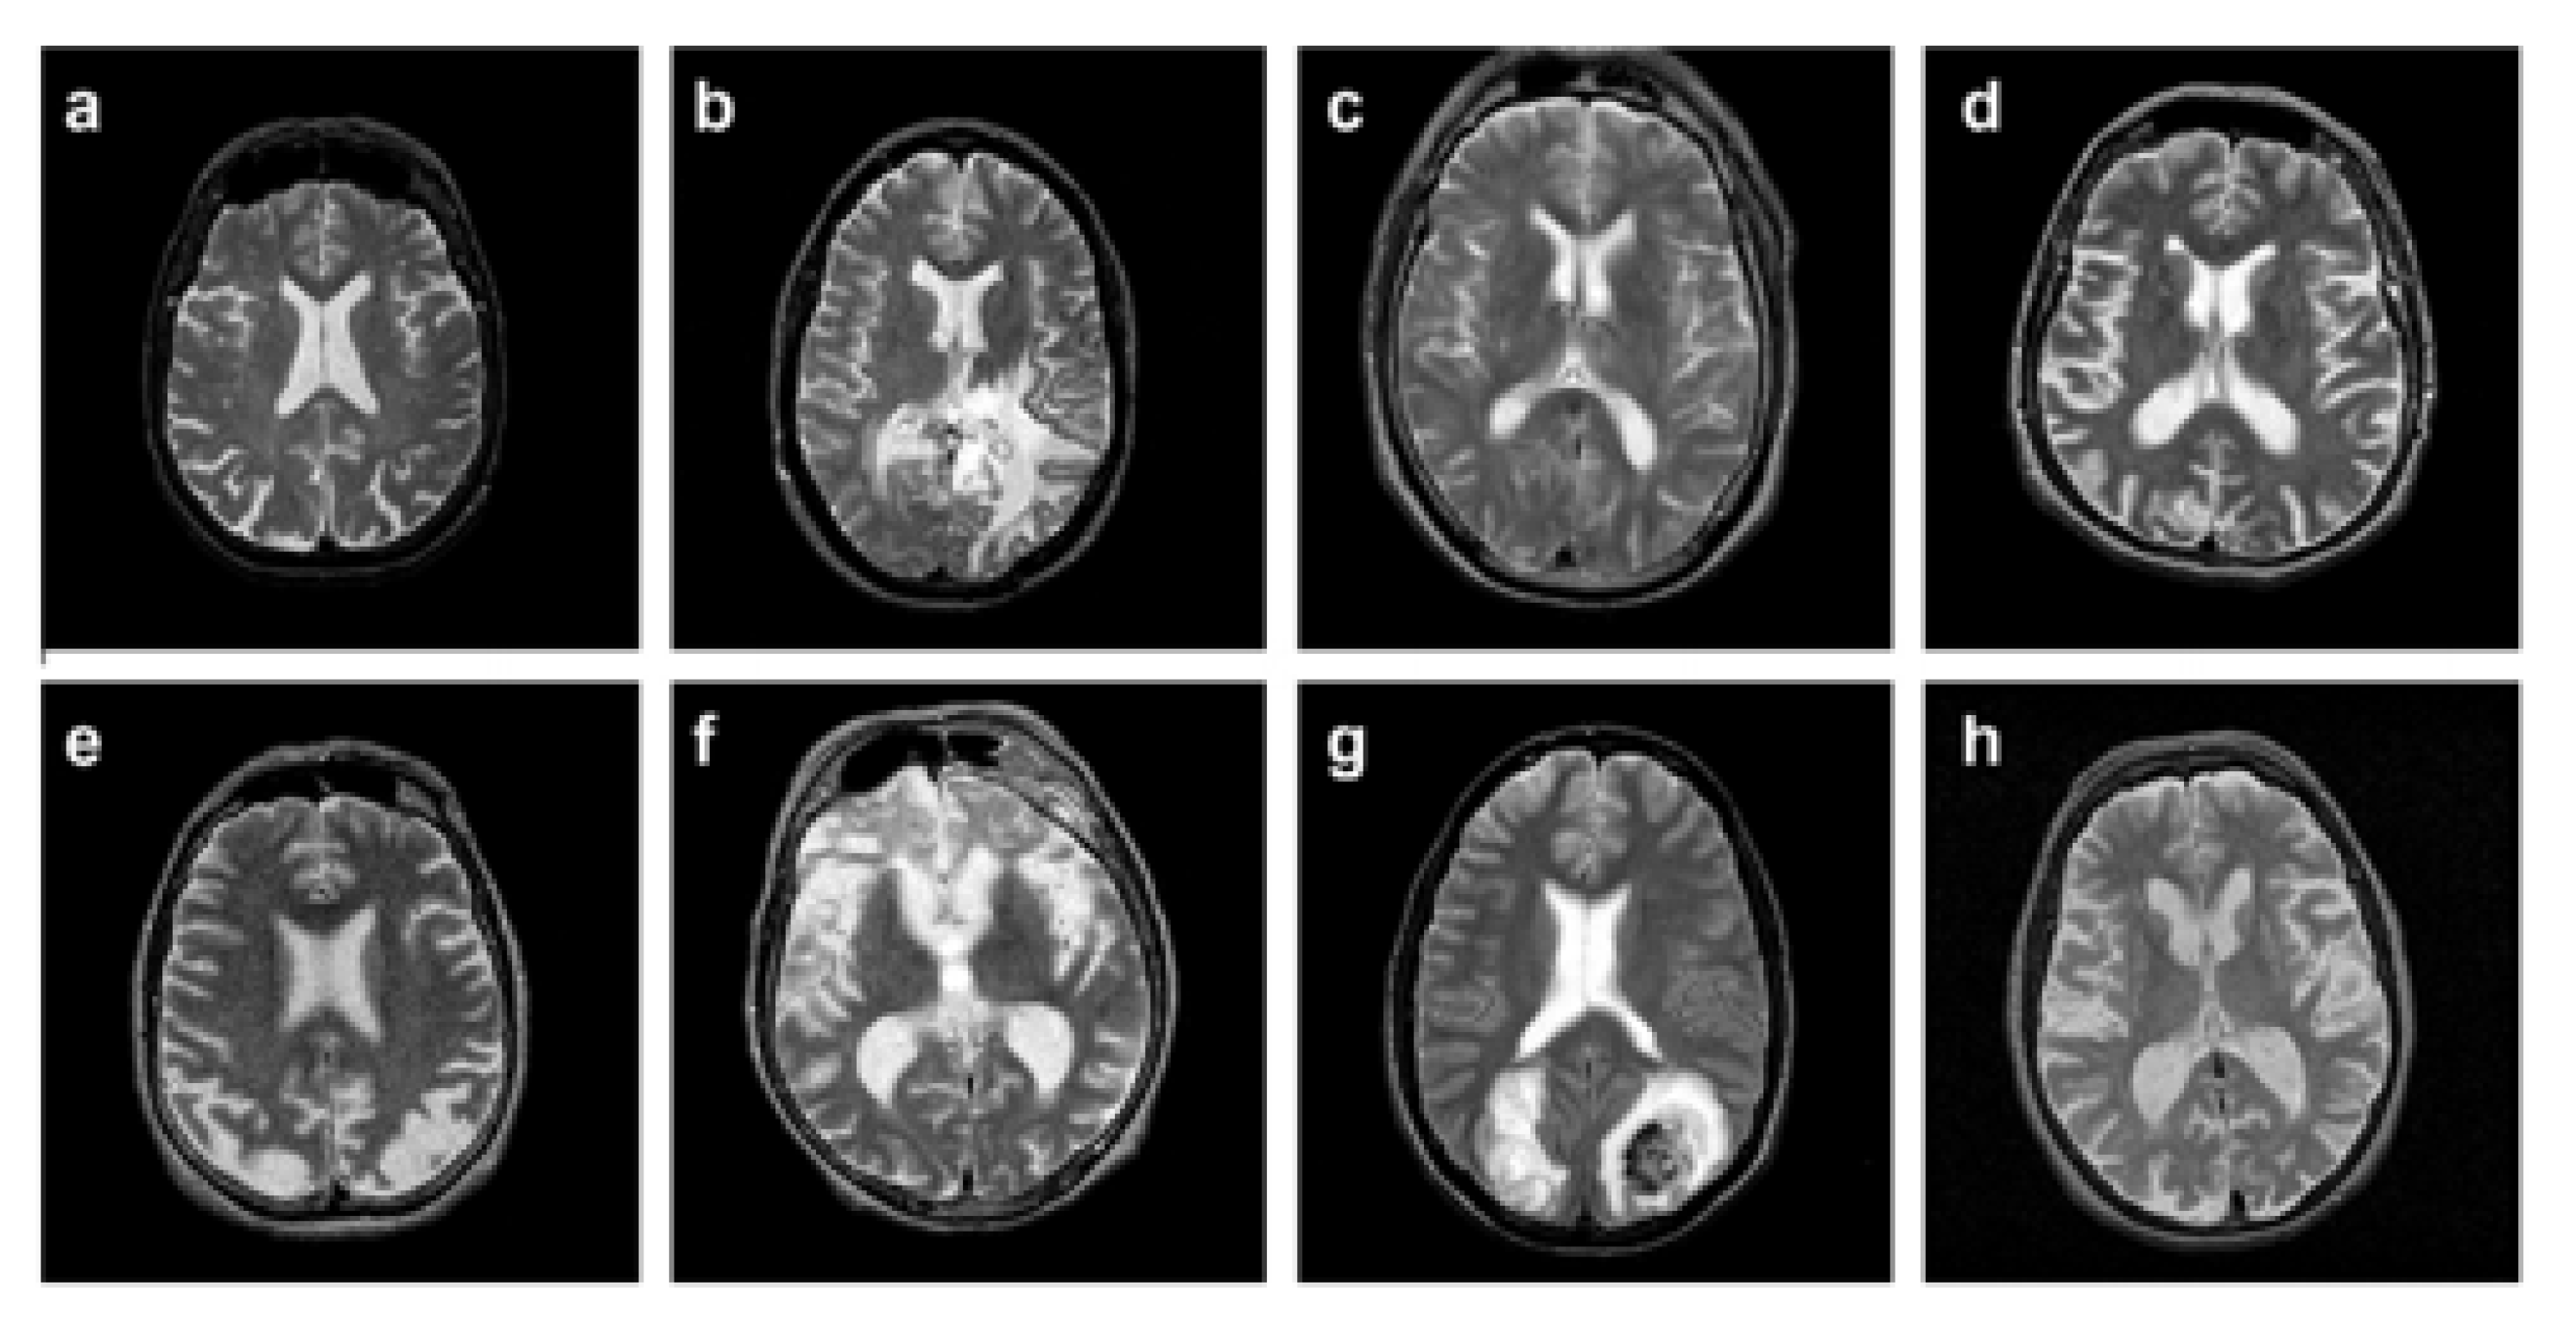

3.1. Preprocessing

4. Implementation, Results, and Explanations

4.1. Implementation Setup